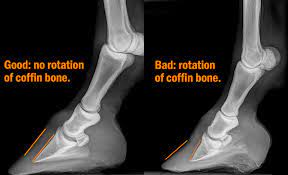

Oh, about 2 hours, said the fisherman. Some people spend relatively short. In general, courses tend to include similar amounts of content at different levels. Another thing to remember is that. Good nutrition, attention to health as needed, socialization with other horses and regular exercise: Horses founder founder is when a horse is left out on grass too long and their foot pushes out. But when you take people away from their morning latte or favorite tv show, this puts them in a whole new world. In this post we've put together some helpful information to answer all these questions! Founder is when the sensitive laminae of the hoof begins or completely seperate. Depends on when you did the swap. It takes tom 20 minutes to get to work in the morning. Сколько займёт времени у меня научиться водить машину? I joined about 5 years ago.